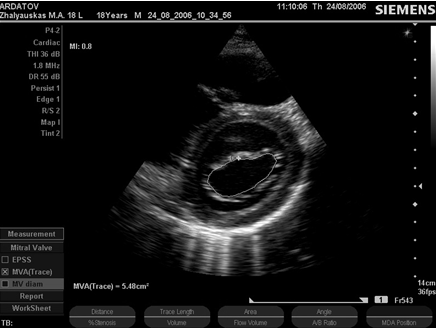

В поперечном парастернальном сечении на уровне митрального клапана (рис. 5) дополнительно оценивают взаимное движение створок, их состояние, форму и размеры митрального отверстия (площадь у взрослых лиц в норме 4 - 6 см2), состояние комиссур.

Рис. 5. В-эхограмма -митральный клапан, поперечное парастернальное сечение, диастола (собственное наблюдение).